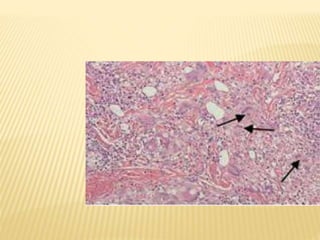

APARICIÓN DE ATEROMAS LOS CUALES SOLO

APARECER EN GRANDES VASOS.

NOTABLE HIPERTROFIA

LESIÓN PLEXIFORME CARACTERÍSTICA DE

HIPERTENSIÓN ALVEOLAR AVANZADA